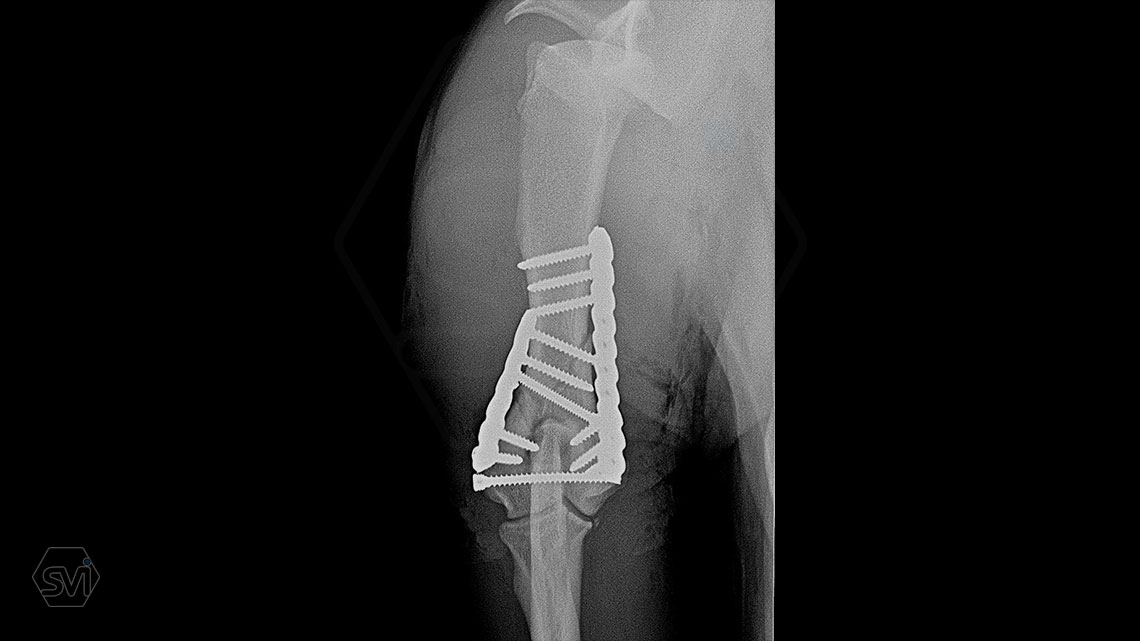

What used to be a nightmare type of surgery is slowly becoming my favorite: the humerus distal Y fracture